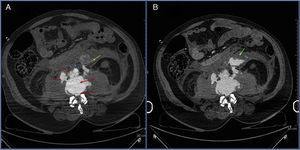

Fifty-six year-old anticoagulated male with ankylosing spondylitis hospitalized after being struck by a car. Patient presents in the hospital with hypovolemic shock, requiring massive blood transfusion and the administration of vasoactive drugs. Negative echo-FAST. The CAT scan confirms aortic rupture secondary to spinal lesion due to a flexion-distraction mechanism. Figures 1 and 2 show axial slices with IV contrast (IVC) in the arterial phase (A), portal phase (B), and sagittal slices in the arterial phase (C) at L2-L3 level. The abdominal aorta shows abundant adjacent hyperdense material consistent with extravasated IVC material (arrows) in the retroperitoneum, the intersomatic space and the epidural space. Patient undergoes urgent surgery that is followed by perioperative death (Figures 1 and 2).